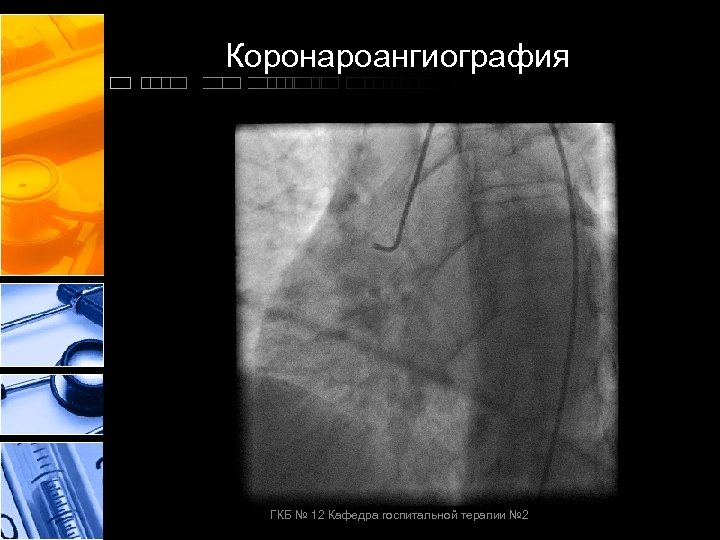

Коронароангиография ГКБ № 12 Кафедра госпитальной терапии № 2